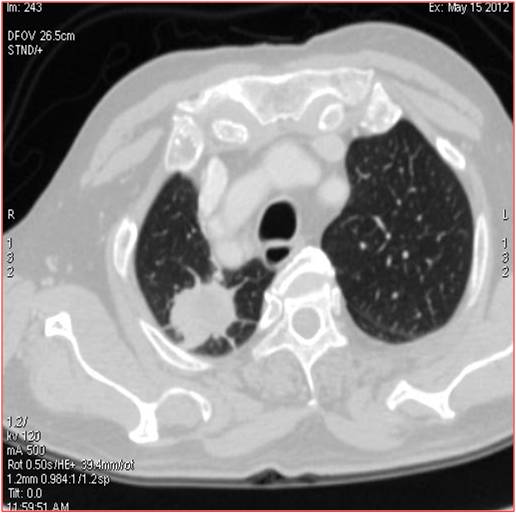

Heterogeneously enhancing irregular spiculated soft tissue mass measuring ~ 34 x 29 mm noted in the apical segment of right upper lobe. The lesion abuts the pleura posteriorly.

FDG avid enhancing lymph nodes noted in right and left paratracheal regions, largest measuring ~ 19 x 11 mm on the right side.

- Metabolically active spiculated right upper lobe lung mass – likely malignant primary.

Mediastinal and retroperitoneal FDG avid metastatic lymphadenopathy.